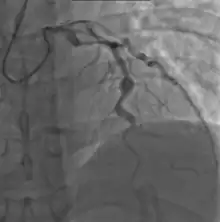

Angiography showing ectatic LAD, with largest aneurysm = 6.5 mm in diameter

Since no specific laboratory test exists for Kawasaki disease, diagnosis must be based on clinical signs and symptoms, together with laboratory findings.[9] Timely diagnosis requires careful history-taking and thorough physical examination.[119] Establishing the diagnosis is difficult, especially early in the course of the illness, and frequently children are not diagnosed until they have seen several health-care providers. Many other serious illnesses can cause similar symptoms, and must be considered in the differential diagnosis, including scarlet fever, toxic shock syndrome, juvenile idiopathic arthritis, and childhood mercury poisoning (infantile acrodynia).[120]

• Angiography was historically used to detect coronary artery aneurysms, and remains the gold standard for their detection, but is rarely used today unless coronary artery aneurysms have already been detected by echocardiography.